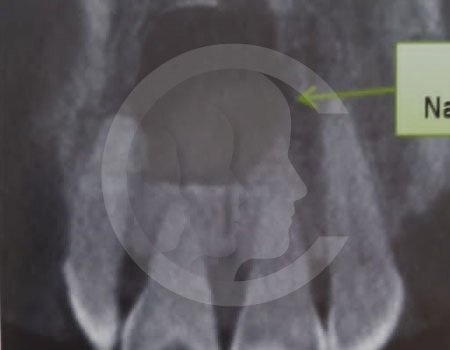

Antes de la extracción se realiza una valoración clínica y estudios de imagen, como radiografías panorámicas o tomografías, para conocer la posición del tercer molar, su relación con los nervios y planificar un procedimiento seguro y adecuado para cada paciente.

No es recomendable. Antes de extraer terceros molares es necesario realizar una valoración clínica y estudios de imagen para conocer la posición del diente, su relación con los nervios y el tipo de procedimiento más seguro para cada paciente.